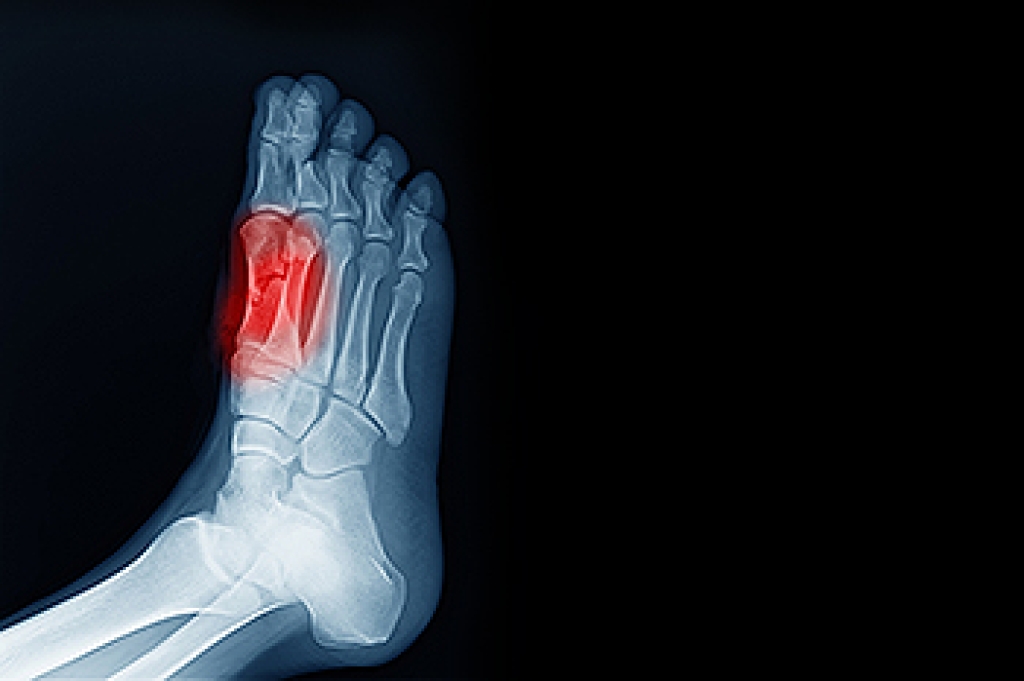

There are bones that are located in the foot which are called the sesamoids. Tendons connect these particular bones to the muscles, and sesamoiditis can happen when these tendons become inflamed. Pain, swelling, and tenderness often accompany this foot condition, and completing daily activities may be difficult to accomplish. The two sesamoid bones are located at the bottom of the foot and big toe, and may also become strained from overuse. People who participate in running and jumping activities may be prone to developing sesamoiditis, and it can be common among dancers. Effective treatment can begin with stopping the activity that caused the injury, and resting the foot as often as possible. Some patients find relief when custom-made orthotics are worn, which may help to provide adequate cushioning. If you have this type of foot pain, please consult with a podiatrist who can properly diagnose and treat sesamoiditis.

Sesamoiditis is a condition of the foot that affects the ball of the foot. It is more common in younger people than it is in older people. It can also occur with people who have begun a new exercise program, since their bodies are adjusting to the new physical regimen. Pain may also be caused by the inflammation of tendons surrounding the bones. It is important to seek treatment in its early stages because if you ignore the pain, this condition can lead to more serious problems such as severe irritation and bone fractures.